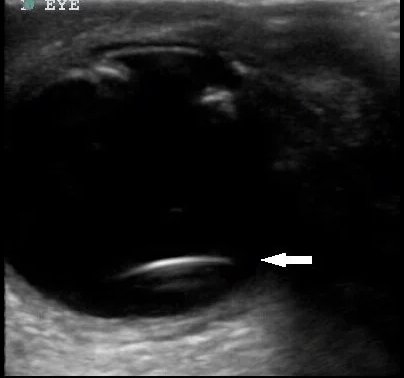

This US finding on ocular US.

What is lens dislocation?